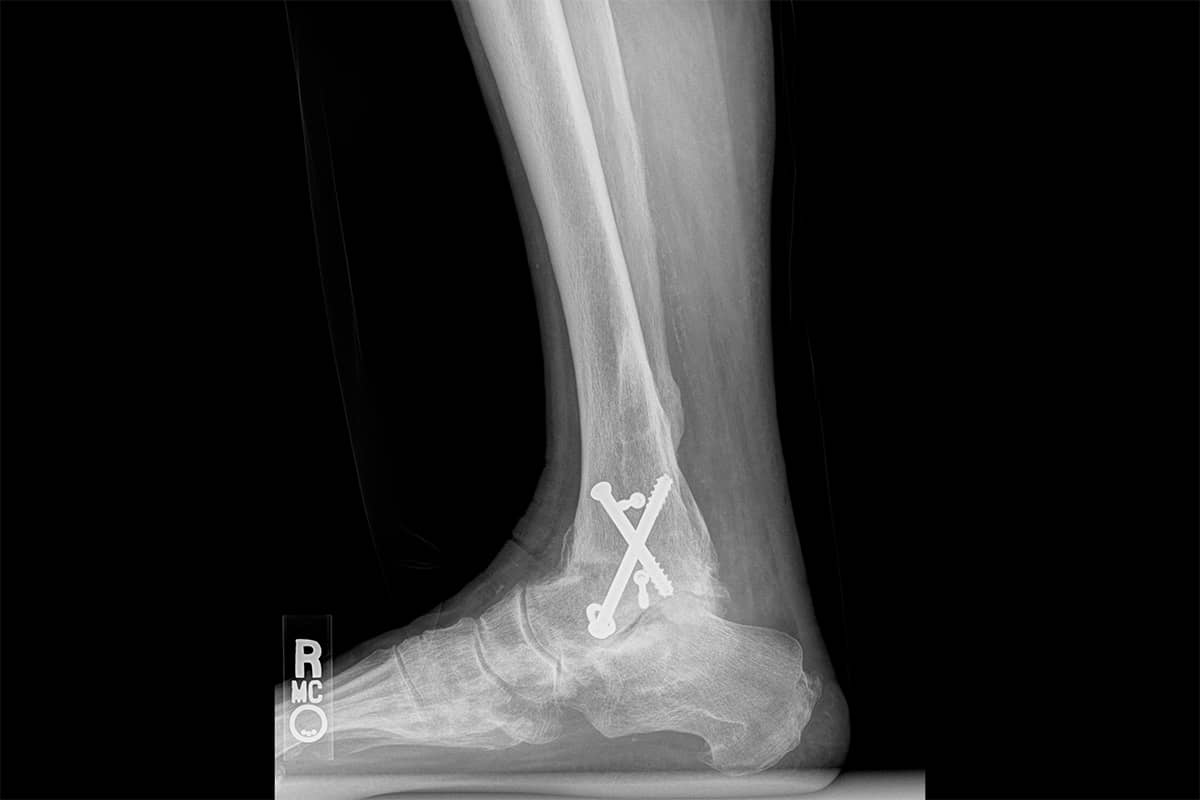

When bones in joints are broken, they sometimes heal poorly. The joint may be misaligned. The cartilage surfaces wear off, and bone-on-bone grinding occurs. Pain at these destroyed joints, especially in the ankle or foot, becomes disabling. The solution offered is often a fusion of the bones to stop the motion: the grinding cycle of pain and inflammation.

Fusion is a failure of our knowledge and skills to find a way to restore motion. When an ankle is fused, the joints below the fusion are subjected to increased loads and abnormal motion. The cartilage wears off, and the joint eventually develops arthritis. The gait of the patient after an ankle fusion is often much better than when the joint was painful, yet it is never normal. The abnormal wear patterns cause problems at the knees, hips, and back as a result of the altered gait mechanics. Artificial joint replacements for the ankle and joints of the foot are uncommon and less successful than replacements at the knee or hip due to the very small bony surfaces that must absorb the entire body’s weight with walking, running, or jumping.

Fusion is often the only choice offered to patients with severe ankle arthritis, and it is both a relief and a failure of science. The failure lies in our inability to restore motion with biologic solutions such as cartilage regeneration. In almost every case in the foot, some options for cartilage repair exist, but they are limited in their use and variable in their success.

We take a dramatically different approach. When presented with these often collapsed and completely worn-out ankle joints, we recreate the joint space, then add a cartilage paste to the exposed bone. This approach works well enough to preserve motion and return many people to varying levels of sports, but it by no means creates a normal joint. Given that the alternative is living with pain or having a fusion, the downside risk seems small.